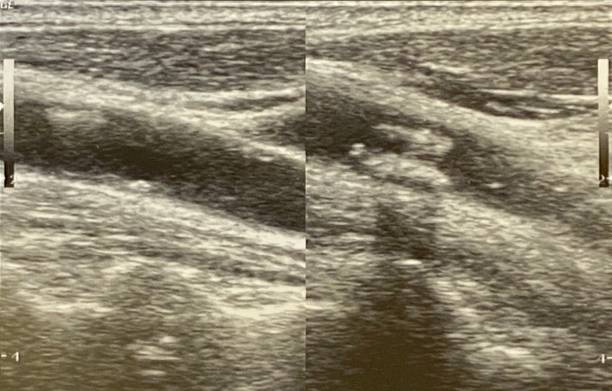

경동맥 초음파 검사는 초음파 기계를 사용하여 경동맥의 상태를 확인하는 검사입니다. 이 검사는 무해하고 비침습적이며, 빠르게 수행할 수 있어 환자에게 불편함을 주지 않습니다. 검사 과정은 다음과 같습니다.

- 초음파 프로브는 고주파 소리파장을 방출하여 경동맥의 이미지를 생성합니다.

- 이미지를 컴퓨터 모니터에 표시하여 의사가 경동맥의 상태를 시각적으로 확인할 수 있습니다.

- 경동맥의 크기와 형태: 경동맥이 충분히 넓고 매끄럽게 유지되는지 확인합니다.

- 혈액 응고물질의 존재: 콜레스테롤과 혈액 응고물질이 경동맥 벽에 쌓여 있는지 확인합니다.